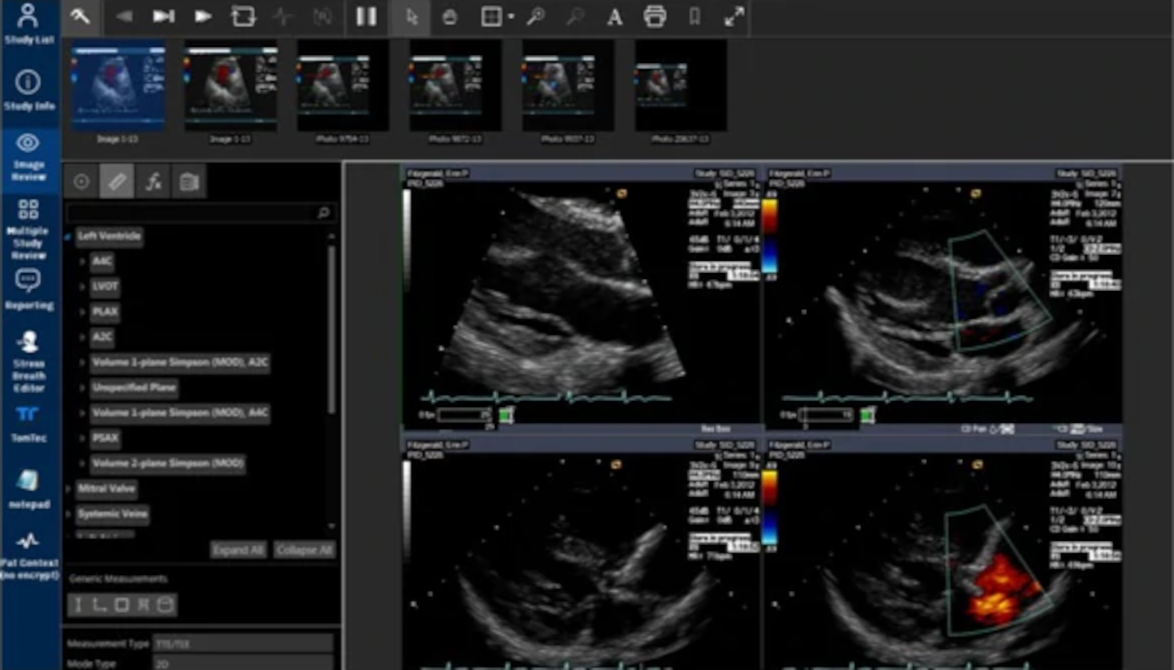

Nearly all types of currently approved AI products represent this type of solution. The very first FDA approved AI device, Cardio DL, is itself marketed as a virtual assistant and much of Arterys' product development work focuses on creating a platform to manage such assistants.

New products that have been released since Cardio DL such as Lung AI, Chest|MSK AI, and Neuro AI provide similar diagnostic support as qXR and LUnit, but couple with workflow automation that comes via integration with the Radiology Information System (RIS), PACS, electronic medical record (EMR), and dictation system. They process DICOM data to generate labels, annotations, heatmaps, and bounding boxes around regions of suspected illness. They then push those labels into the medical IT infrastructure to help prioritize the review of studies that may have abnormal findings and emphasize aspects of the study that may be concerning.